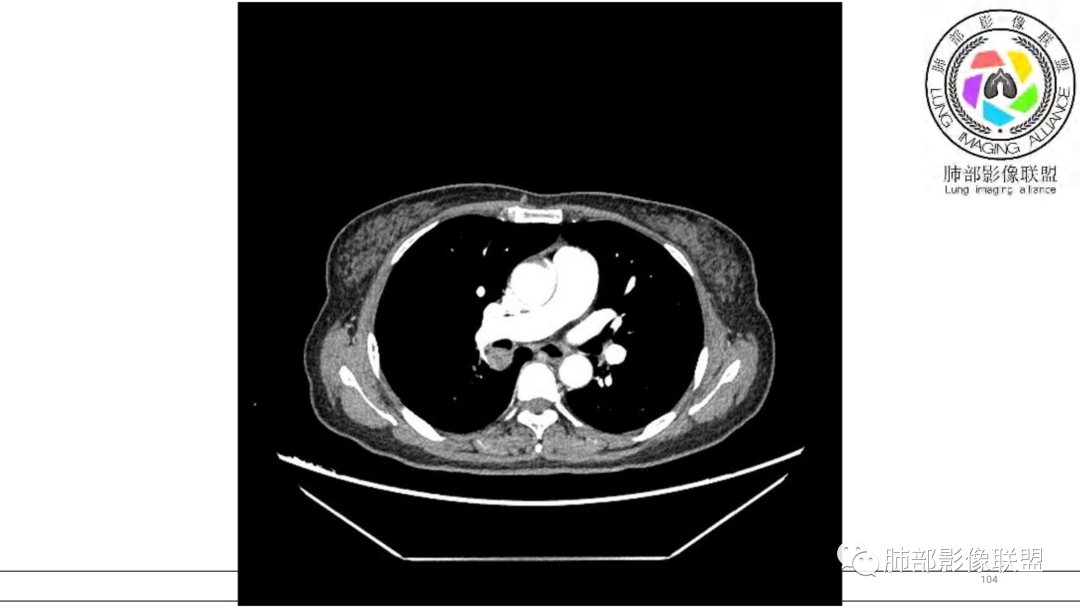

2.右肺下叶及中间段支气管后方类圆形块影,边界较清楚,未见分叶及毛刺,病灶部分突入支气管腔内(冰山一角),局部管腔狭窄,相应肺叶未见片影或体积变化。

3.块影密度均匀,未见液化坏死及钙化,渐进性强化,强化显著。

中青年女性,支气管管腔内外肿块(“冰山征”),边界较清楚,强化显著,未见阻塞性肺不张,尽管未出现“类癌综合征”临床表现,仍然符合典型类癌影像学表现。

类癌临床表现无特异性,影像学检查仍然是肺类癌的主要诊断依据。其特征性表现是孤立的、边界清楚的肿物,密度可均匀或不均匀,边缘多清楚锐利,部分病例可见浅分叶及毛刺。类癌侵及的支气管局部增厚,与正常的管壁分界清楚,局部呈乳头状突起,表面光滑。肺门旁肿块往往边缘光整、轮廓清楚、密度均匀,增强扫描大多呈均匀明显强化,可有持续强化或延迟强化。中央型肺类癌可引起支气管壁局限性增厚,形成轮廓光滑的管壁结节,并与腔外大病灶形成“冰山征”。少数病例可沿支气管腔内长轴生长,呈指套样改变,类似肺鳞癌,但较肺鳞癌血供丰富。